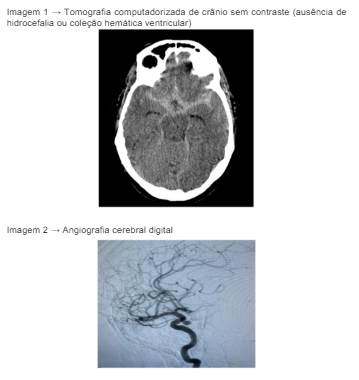

Paciente do sexo feminino, 53 anos, auxiliar de serviços gerais, tabagista 30 anos-maço, hipertensa em tratamento irregular, apresentou cefaleia súbita holocraniana ao ir trabalhar. Foi levada, de imediato, ao hospital referência mais próximo. Na admissão, chegou com abertura ocular e com movimentos de flexão normal ao estímulo doloroso da região glabelar e resposta verbal com frases completas e desconexas da realidade. Anisocoria – esquerda maior que direita e pupila esquerda não ofotoreagente. Apresentava-se com rigidez nucal e sinal de Brudizinski. Foi realizado estabilização imediata e exames de imagem.